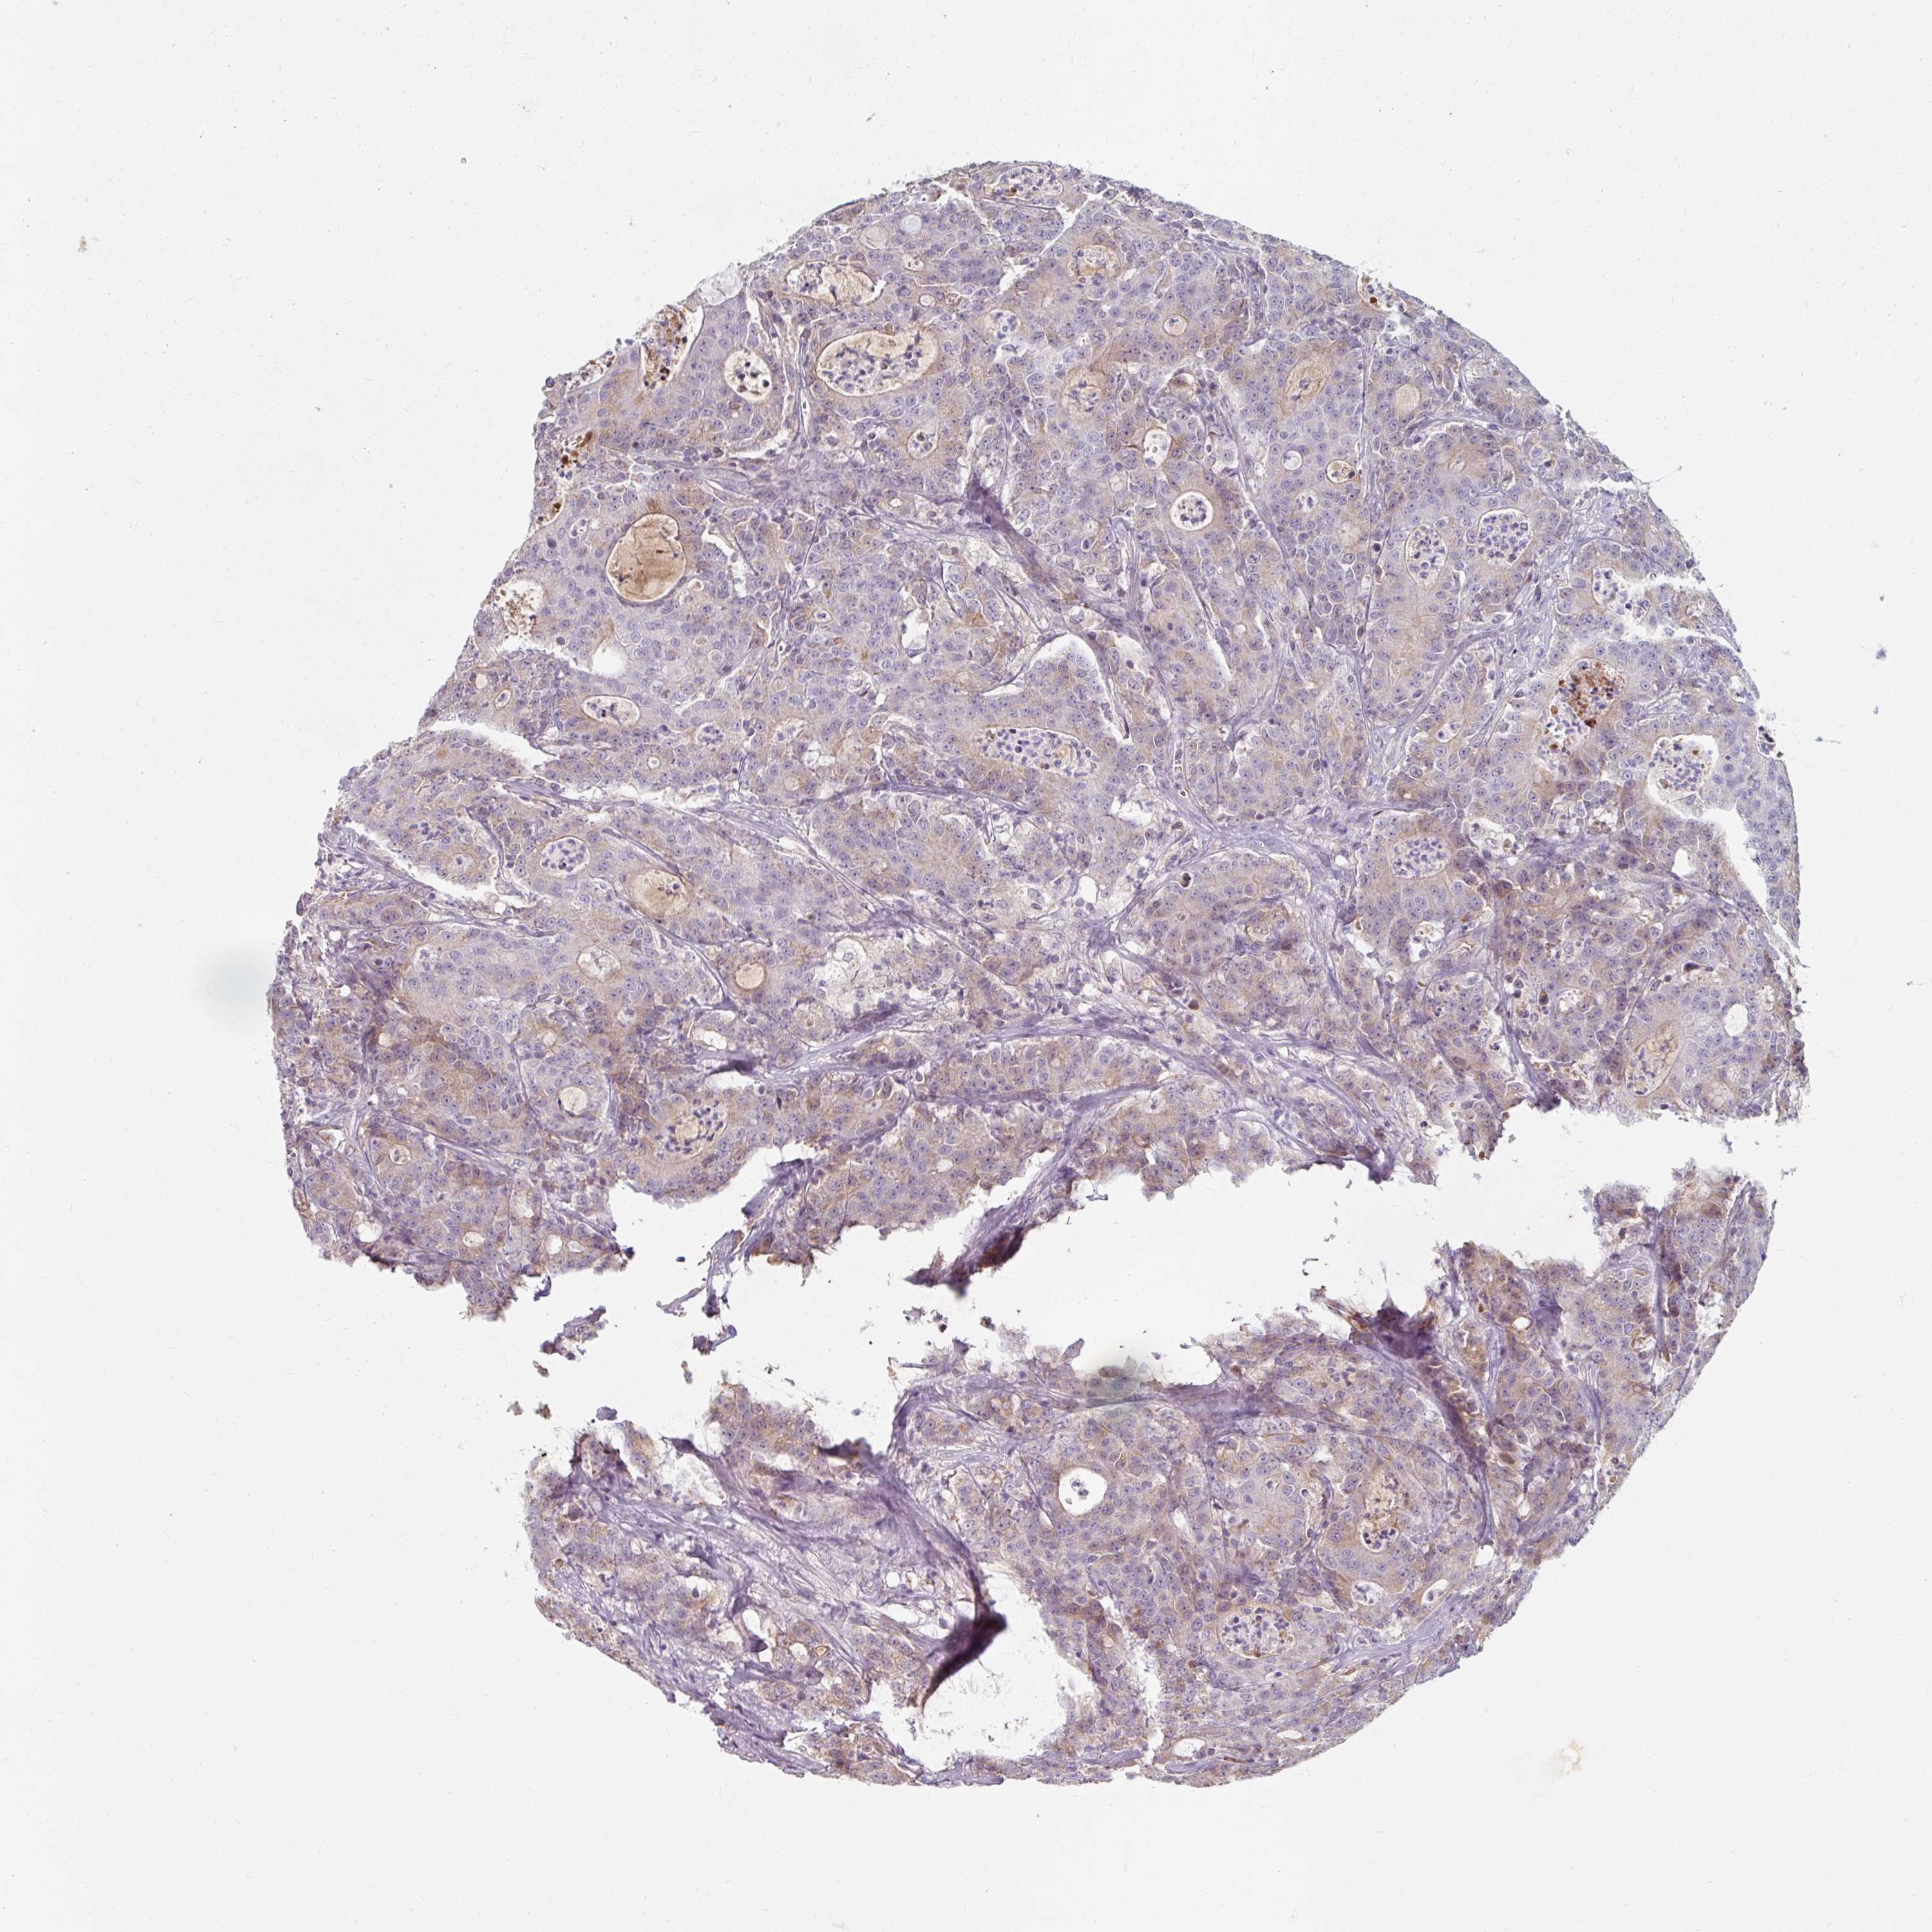

CANCER COLORECTAL CANCER Show tissue menu

Colorectal cancer

Human cancer

Rectum adenocarcinoma